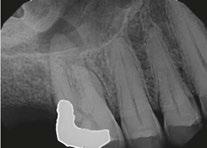

The patient was diagnosed with irreversible pulpitis in tooth number 14, which presented multiple canals with highly complex anatomies. All canals were instrumented to 25/.04 and cleaned with Odne®Clean following the recommended clinical protocol. The use of Odne®Clean enabled the identification of five canal orifices and clearing of apical deltas.

Clinical case performed by Dr. Benedict Bachstein (Figures 1-3)